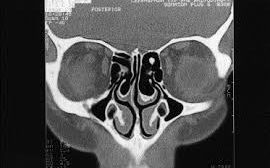

Günümüzde paranazal sinüs patolojilerinin radyolojik tanısında bilgisayarlı tomografi (BT) altın standart olarak kabul edilmektedir.